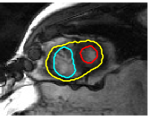

The problem above is a generalization of Horn & Schunck optical flow. Note that solving for the Horn & Schunck optical flow within each region separately does not lead to motions such that at the interface, they have equal normal components (see Figure 1), whereas the solution of (5) to be presented in subsequent sections does. Note that computing Horn & Schunck optical flow in each region requires boundary conditions (and typically they are chosen to be Neumann boundary conditions: and on ). Note that replacing these boundary conditions with the boundary constraint (6) does not specify a unique solution. Also, while Horn & Schunck optical flow computed on the whole domain naturally gives a globally smooth motion, which by default satisfies matching normals at the interface, this is not natural for the ventricles / myocardium, where different motions exist in the regions (see Figure 2), and the motions should not be smoothed across the regions.

![]() |

| image + boundary | next image | within region optical flow | our method |